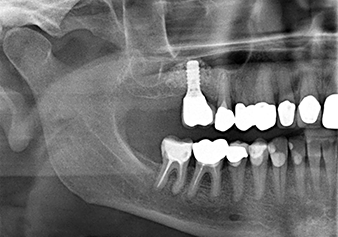

The x-ray check shows a largely homogeneous peri-implant hard tissue structure

Fig.10: A good six months later, after the definitive crown had been incorporated, the x-ray check shows a largely homogeneous peri-implant hard tissue structure.